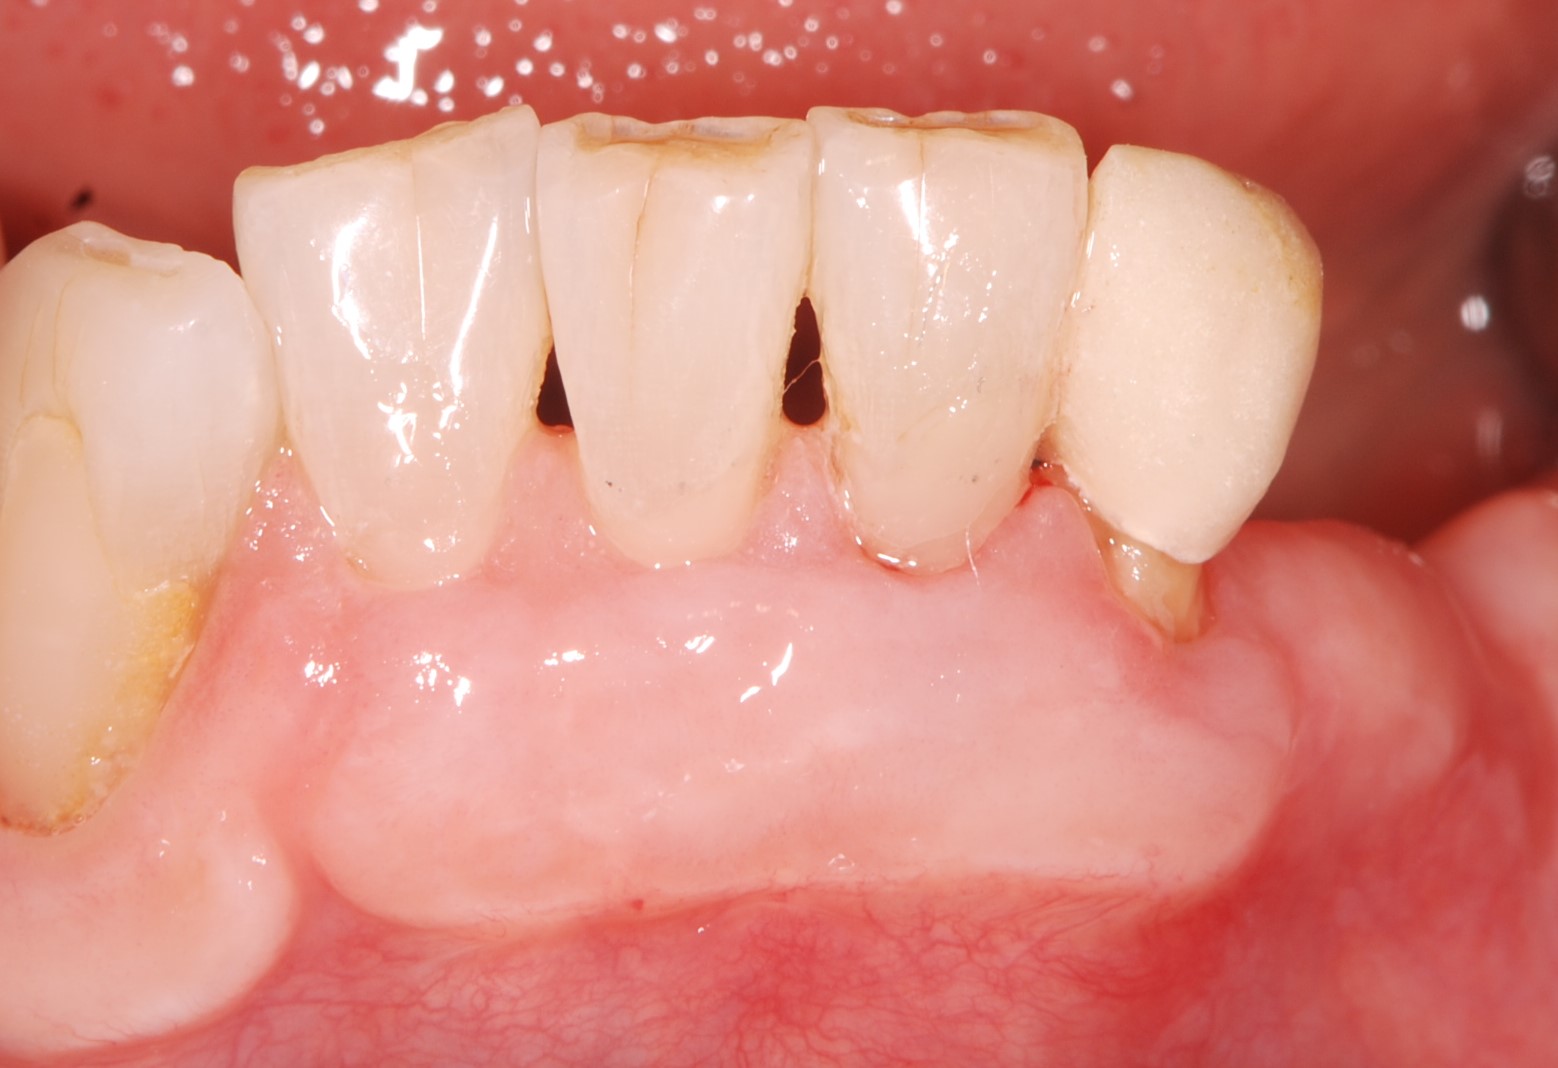

• 治療前

古い詰め物と虫歯を取った状態。血管が透けて見えるほど薄い歯茎である。このような歯茎は歯ブラシが当たると痛みを感じやすい。